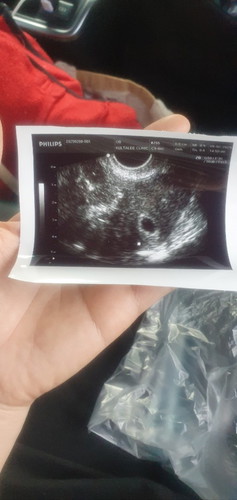

#ขอโทษที่แม่ดูแลลูกไว้ไม่ได้💔😭 #แม่จะรอหนูกลับมาหาแม่กับพ่อกับพี่ชายนะคะ❤️ #วันที่ 04/02/2568 ผลตรวจครรภ์ท้อง พ่อแม่พี่ชายครอบครัวดีใจมากที่มีสมาชิกเพิ่มหลานน้อยเพิ่ม ตกลงจะไปฝากครรภ์ให้โตขึ้นมาอีกนิดช่วงปลายเดือนกุมภาพันธ์ ดีใจได้ 4 วัน #วันที่ 07/02/2568 กลางคืนมีเหตุการณ์เลือดออกสีน้ำตาลนิดหน่อย #วันที่ 08/02/2568 ช่วงเช้ายังคงมีเลือดสีน้ำตาลเข้มออกมา จึงรีบพากันไปหาหมอที่คลีนิค หมออัลตร้าซาวด์ยังไม่พบน้อง พบแต่ถุงน้ำคร่ำ เนื่องจากอายุครรภ์ 7Week3Day หมอจึงบอกบางทีน้องน่าจะตัวเล็กจึงทำให้ยังมองไม่เห็นน้อง จึงนัดรออีก 2Week ในวันที่ 22/02/2568 ค่อยมาอัลตร้าซาวด์อีกรอบ หมอจึงฉีดยากันแท้งและให้ยากันแท้งกับยาโฟลิคมากิน #วันที่ 09/02/2568 ยังคงมีเลือดสีน้ำตาลเข้มออกมาอยู่ จนถึงกลางคืนช่วงเวลา 2 ทุ่ม จากเลือดสีน้ำตาลเข้มเริ่มกลายเป็นสีแดงซึ่งเริ่มออกมาเยอะ และมีอาการปวดท้องน้อยนิดๆ คล้ายปวดประจำเดือน แม่ก็รีบโทรปรึกษากับทาง รพ. แต่ดันตรงกับวันอาทิตย์ และเป็นช่วงดึก ทาง รพ. จึงแนะนำให้มาพบหมอในเช้าวันจันทร์ ที่ 10 แนะนำให้แม่นอนนิ่งๆ ไปก่อน เพราะได้มีการฉีดยากันแท้งและกินยากันแท้งแล้ว #วันที่ 10/02/2568 ช่วงเช้าแม่ลุกเข้าห้องน้ำ ก็เกิดเหตุการณ์ไม่คาดฝัน เลือดสีแดงสดแม่ออกมาเยอะมาก แล้วก็มีชิ้นเนื้อหลุดออกมา แม่ก็ตกใจมาก รีบไปหาหมอ แต่ประจวบเหมาะกับลูกชายคนโตก็หกล้มฟันโยกที่โรงเรียน คุณครูที่โรงเรียนโทรมาแจ้ง และเวลานั้นทางครอบครัวก็ไม่มีใครอยู่บ้านเพราะไปงานขาวดำญาติกัน แม่โทรติดต่อใครก็ไม่รับสาย แม่จึงรีบไปรับลูกชายคนโตที่โรงเรียนเองเพื่อพากลับมาบ้าน จากนั้นพี่สาวกับยายกลับมาบ้านพอดี ก็พาลูกชายคนโตไปพบหมอฟัน และก็รีบพาแม่ไปพบหมอทันที พอหมอตรวจดู ก็ไม่ทันแล้ว น้องได้จากแม่พ่อพี่ชายและครอบครัวไปแล้ว เหลือเพียงแต่เศษรกเศษถุงน้ำคร่ำที่หลุดออกมา หมอจึงทำการนัดแม่มาตรวจพร้อมกับการขูดมดลูกอีกครั้งในวันที่ 11/02/2568 ให้แม่งดน้ำงดอาหารตั้งแต่เวลา 00.00 เป็นต้นไป #วันที่ 11/02/2568 คุณหมอได้ทำการตรวจแม่อีกครั้งและจำเป็นต้องทำการขูดมดลูกเพราะชิ้นส่วนรกถุงน้ำคร่ำออกไม่หมด ไม่งั้นจะเป็นอันตราย #4วันกับการสร้างรอยยิ้มเสียงหัวเราะความดีใจให้กับครอบครัว #4วันหลังต้องตกใจและเสียใจพร้อมทั้งน้ำตาที่เป็นความทรงจำที่ใจสลายมาก💔😭 #8วันที่มีทั้งรอยยิ้มเสียงหัวเราะความตกใจความเสียใจมีน้ำตาท่วมท้นที่ใจสลาย💔😭 #ภาวะแท้ง #ท้อง2 #ยุติการตั้งครรภ์